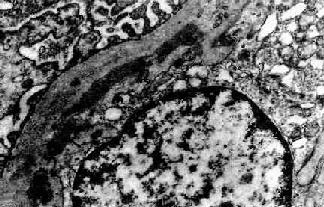

图12-13 膜性增生性肾小球肾炎 肾小球系膜细胞增多,增生的系膜组织侵犯毛细血管,毛细血管壁增厚,腔狭小,肾小球丛呈分叶状 电镜观察可见肾小球系膜增生,毛细血管基底膜不规则增厚。增生的系膜组织沿毛细血管基底膜和内皮细胞之间向毛细血管周围部分伸展,甚至环绕全部毛细血管壁,使毛细血管壁增厚。肾小球内有大量电子致密物沉积。根据沉积物的部位,可将膜性增生性肾小球肾炎分为3型: Ⅰ型电子致密物沉积在肾小球基底膜内侧,内皮细胞下,大小不等,常聚积成大团块状(图12-14,图12-15)。系膜内和上皮细胞下偶然也可见有少量小而不规则的沉积物。

图12-15 膜性增生性肾小球肾炎 Ⅰ型 肾小球毛细血管基底膜内侧,内皮细胞下电子致密沉积物,部分上皮细胞足突消失 Ⅱ型肾小球毛细血管基底膜不规则增厚。在基底膜致密层内有高电子密度的粗大呈带状的沉积物(图12-16)。故这型肾炎又称为致密沉积物性肾小球肾炎或致密沉积物病。